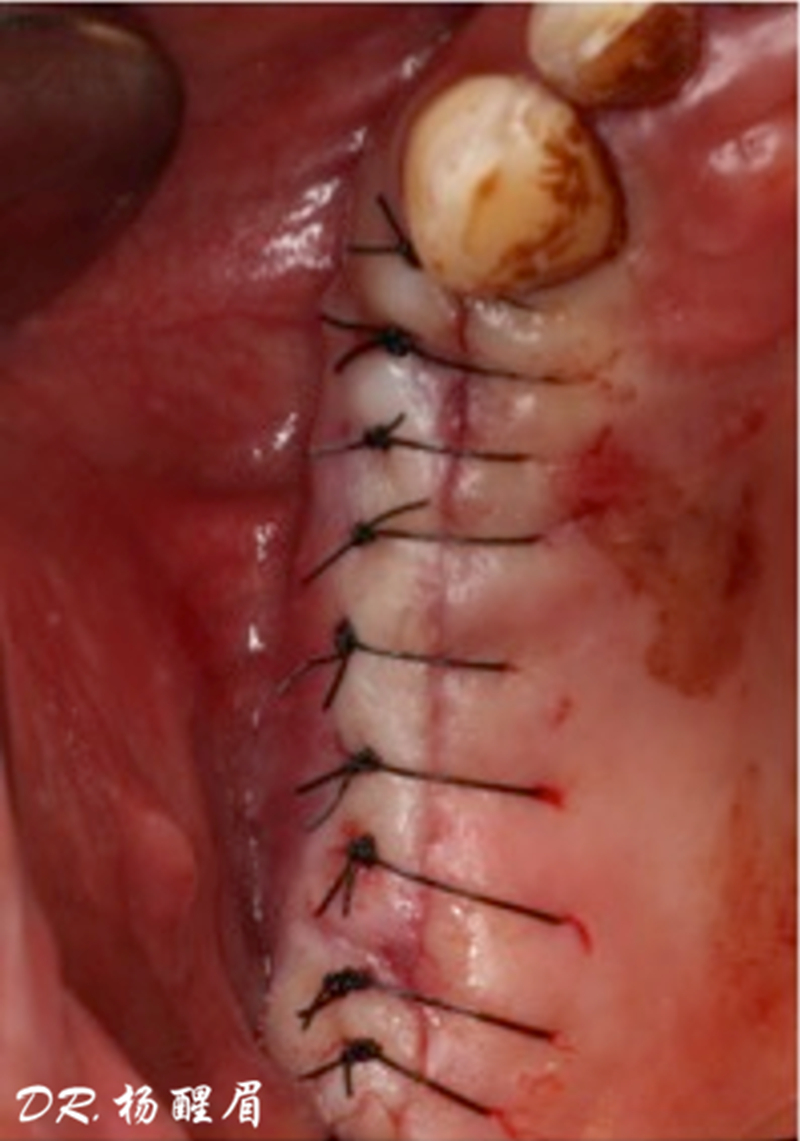

®完成3顆植體的植入,植體位點如術前方案設計,均在同軸線。

®進行縫合

®多顆植體位點及角度的精確性,確保后期修復方案順利完成,也使患者能在使用過程中承受最佳的咬合力